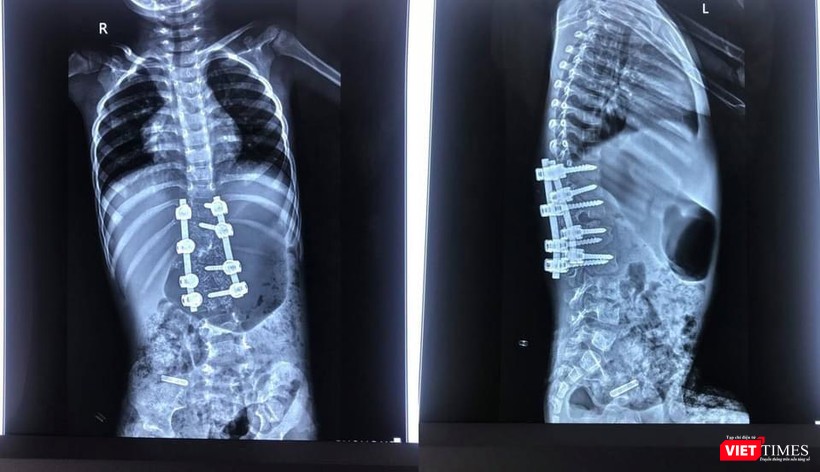

| Hình ảnh X quang ca cong vẹo cột sống của bệnh nhi 3 tuổi (BVCC) |

Bác sĩ cho biết sau phẫu thuật biến dạng được nắn chỉnh rất tốt |

Hình ảnh X-quang sau mổ cho thấy biến dạng được nắn chỉnh rất tốt, còn giữ được chức năng 3 đĩa đệm cuối cùng của cột sống thắt lưng. Ca phẫu thuật thành công mang lại một dấu mốc với khoa Chấn thương - Chỉnh hình Cột sống (B1-D) và khoa Gây mê hồi sức (B5) của BV 108, mở ra cơ hội cho nhiều bệnh nhi khác.